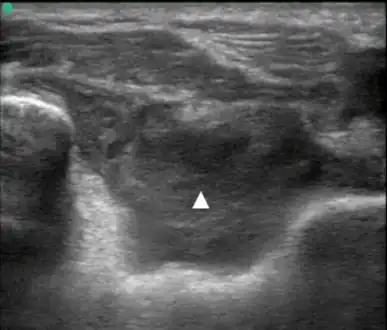

Posterior transverse view of the elbow with hemarthrosis

Synovial Fluid analysis is another method to diagnose Hemarthrosis. It involves a small needle being inserted into the joint to draw the fluid.[8] Reddish-colored hue of the sample is an indication of the blood being present. Imaging tests are normally done. The tests also include MRI, Ultrasound and X-ray test, which give better information about the joint inflammation.[9]